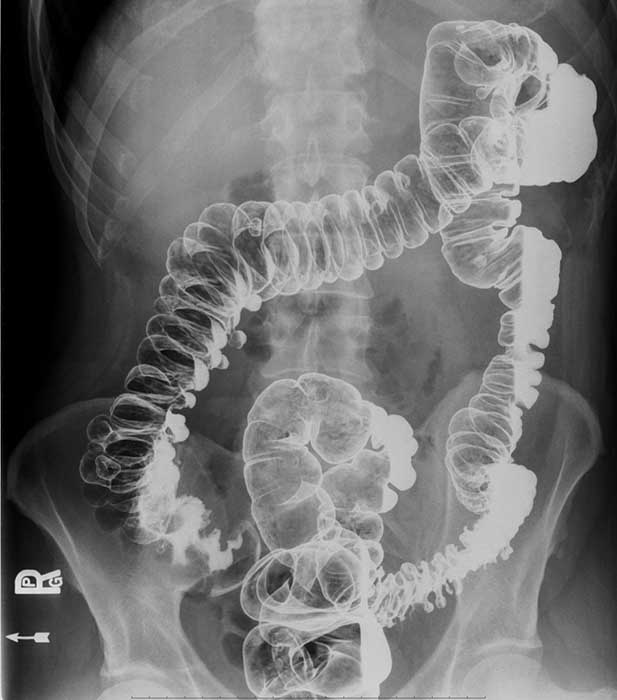

What is volvulus? (twist)

A twisting of a portion of the bowel that may cause obstruction and compromise blood supply.

Where does volvulus most commonly occur?

In the cecum and sigmoid colon. (image shows cecal volvulvus)

How does cecal volvulus occur?

The cecum twists on its long axis and often displaces upward and to the left.

How does sigmoid volvulus occur?

The sigmoid twists on its mesenteric axis, rotating left or right.

What are the two major dangers of volvulus?

Bowel obstruction and compromised blood supply.